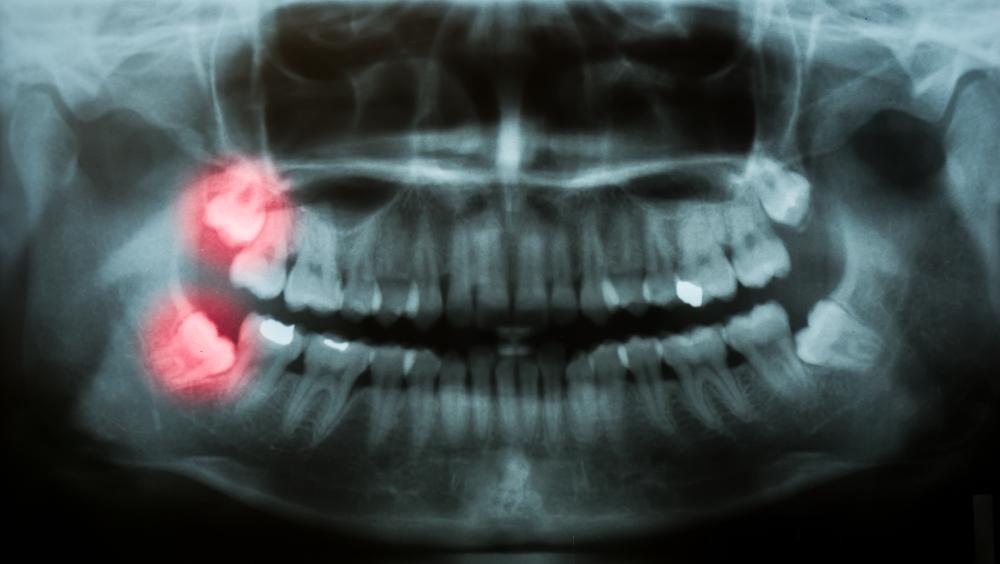

Digital x-rays are simple and painless for patients. First, we place a small digital sensor in your mouth to capture an image of your teeth and jaws. We move the sensor around each section of your mouth, so we get a full map of your mouth. The sensor then sends the images to our treatment room monitors, where we can instantly view your teeth, jawbones, and any underlying structures like unerupted or impacted wisdom teeth. In a matter of minutes, you and your dentist can see x-ray images of your entire oral cavity.